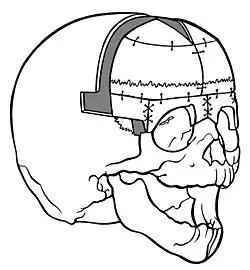

Trigonocephaly

Trigonocephaly is a congenital condition due to premature fusion of the metopic suture (from Ancient Greek metopon 'forehead'), leading to a triangular forehead. The premature merging of the two frontal bones leads to transverse growth restriction and parallel growth expansion. It may occur as one component of a syndrome together with other abnormalities, or in isolated form. The term is from Ancient Greek trigonon 'triangle' and kephale 'head'.

Diagnosis

Diagnosis can be characterized by typical facial and cranial deformities.[2][19]

Observatory signs of trigonocephaly are:

- a triangular forehead seen from top view leading to a smaller anterior cranial fossa

- a visible and palpable midline ridge

- hypotelorism inducing ethmoidal hypoplasia

Imaging techniques (3D-CT, röntgenography, MRI) show:

- epicanthal folds in limited cases

- teardrop-shaped orbits angulated towards the midline of the forehead ('surprised coon' sign) in severe cases

- a contrast difference between a röntgenograph of a normal and a trigonocephalic skull

- anterior curving of the metopic suture seen from lateral view of the cranium on a röntgenograph

- a normal cephalic index (maximum cranium width / maximum cranium length) however, there is bitemporal shortening and biparietal broadening